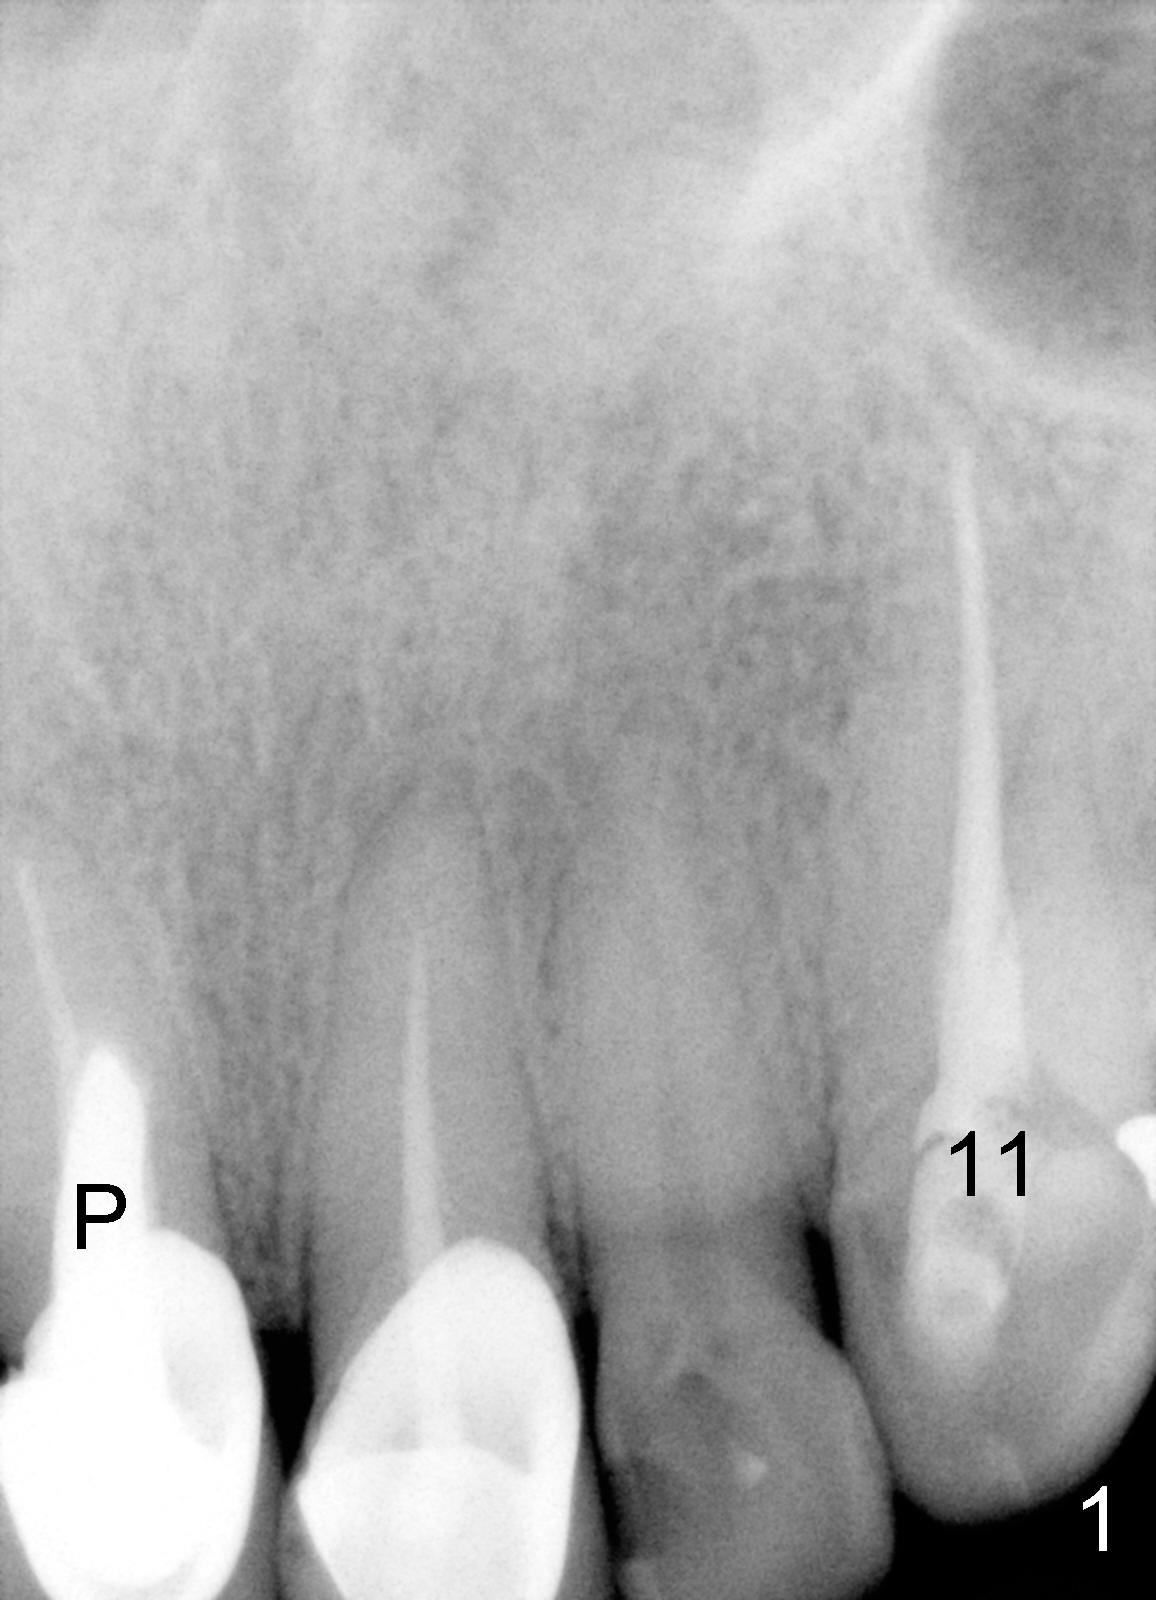

Fifty-five-year-old lady became my patient 6 years ago because of RCT for #11 (Fig.1). At that time, #8 had a large and malpositioned post (P), whereas #9 did not have a post. Since then, she has returned for recementation of crowns for several times. Recent X-ray shows that #8 has had apicoectomy (black * in Fig.2) and large radiolucency on the side of the root (white *, which was absent 6 years ago, as compared to Fig.1). The tooth #9 crown is loose with subgingival margin. It appears that both incisors are nonsalvageable.